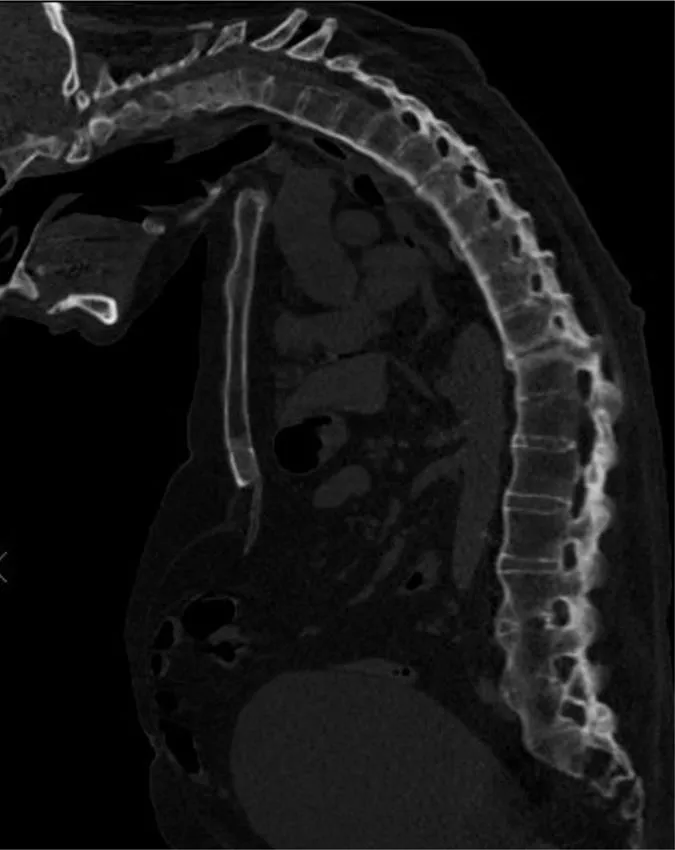

- 2. CT whole spine:

- a. Ossification of anterior longitudinal ligament

- b. Fusion of multiple facet joints

- c. Severe cervicothoracic kyphosis

- d. Fracture line starting at D5/6 intervertebral disc and extending into the posterosuperior body of D6 and D6/7 facet joints

- e. Mild retrolisthesis of D5 over D6

- f. Widened lucent line through D10/11 disc space and facet joints with adjacent reactive sclerosis

- g. Distended urinary bladder.

- 1. Ankylosing spondylitis, acute fracture through D5/6 extending through the posterior elements. This is an unstable fracture as all three vertebral columns are disrupted.

- 2. Pseudoarthrosis D10/11, most likely secondary to non-union of an old fracture.

Ankylosing spondylitis is a regular feature of the FRCR 2B examination, either as a written case or in the viva. The scenarios involved could be bilateral symmetrical sacroiliac joint erosion, sclerosis or fusion, erosion of the anterosuperior corner of the vertebra on lateral radiograph (Romanus sign), sclerosis of the anterosuperior corner and periostitis of the waist giving rise to vertebral ‘squaring’, syndesmophyte formation leading to ‘bamboo spine’, intervertebral disc calcification, ossification of the anterior longitudinal, posterior longitudinal, interspinous and supraspinous ligaments, kyphosis and facet joint fusion. Other skeletal features include erosions of the symphysis pubis and ischial tuberosities, asymmetrical erosive oligoarthritis, atlanto-axial dislocation and osteoporosis. In a traumatic setting, the fracture line may run through the intervertebral disc space right through into the posterior elements, and may be missed if one is not vigilant. Clinically occult fractures can also occur, leading to mobile non-union (pseudoarthrosis) – the so-called Anderson lesion.